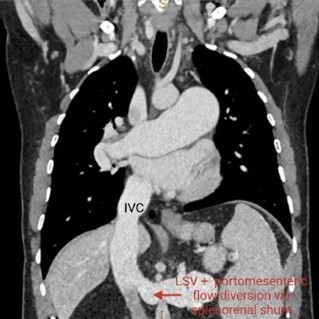

• Imaging “Mini-Atlas” of Vascular Liver Diseases

Rita Trovisco, Prof. Manuela França

48-59

DOI: https://doi.org/10.60591/crspmi.560